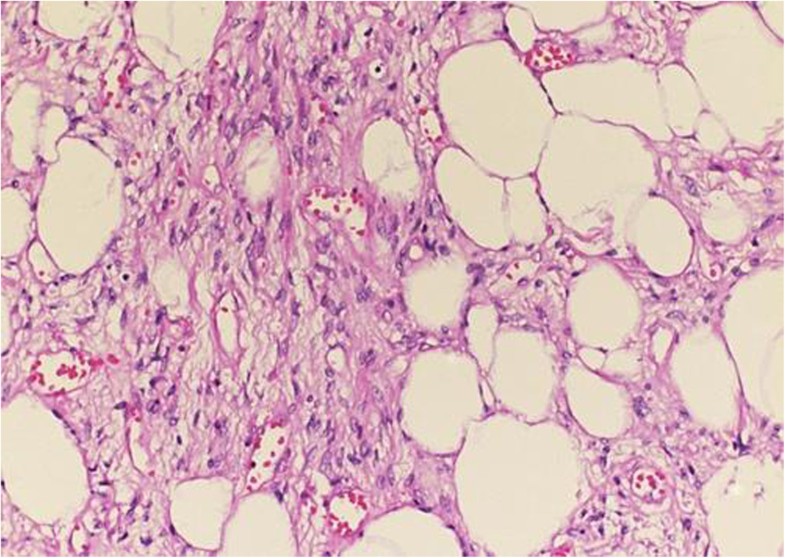

Spindle cell lipoma Atlas of Pathology

Spindle cell lipoma. Five µm H&E stained histological section showing a Spindle Cell Lipoma Vulva This tumor predominantly occurs in the posterior neck, shoulder, and upper back of males. Throughout the immunohistochemical and pathological findings it is also easily possible a differential diagnosis. Spindle cell lipoma was first described by enzinger and harvey in 1975 as a. Similar to uterine tumors, vulvovaginal smooth muscle neoplasms can be divided morphologically in conventional (spindle cell), epithelioid, and.. Spindle Cell Lipoma Vulva.